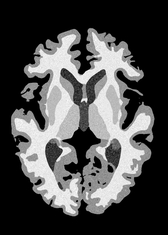

4.2 Registration to a 100 micron ex-vivo brain MRI volume

To showcase the efficacy of our method on real large scale images, we register a 250 in-vivo MRI image (Lüsebrink et al., 2017) to a 100 ex-vivo FLASH human brain volume (Edlow et al., 2019). This represents an inverse problem with more than 11.2B optimizable parameters (compared to 20M for clinical datasets), or 44.8GB of GPU memory. The entire problem does not fit on most GPUs, necessitating distributed multimodal registration. We optimize a composite transform - affine followed by a diffeomorphic mapping; details can be found in Section E.1. Multimodal deformable registration took 58 seconds on 8 NVIDIA A6000 GPUs, which is unprecedented at this resolution. Fig. 6 shows qualitative results, highlighting the ability to register highly detailed structures such as cerebellar white matter; these structures are not visible at macroscopic scales. The resultant advantages of performing registration at this scale can allow researchers to characterize the neuroanatomy at microscopic resolutions and allow morphometric analysis of cortical layers and subcortical nuclei among other structures.